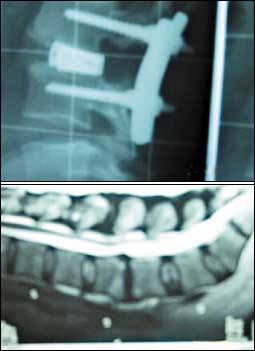

ألم العمود الفقري ..الوقاية والعلاج

يعتبر ألم العمود الفقري سواء الألم أسفل الظهر أو في منطقة الرقبة من أكثر الأمراض شيوعا في مجتمعنا، فبعض هذه الآلام قد يكون حميداً ويكون دائماً نتيجة ل.........

التفاصيل